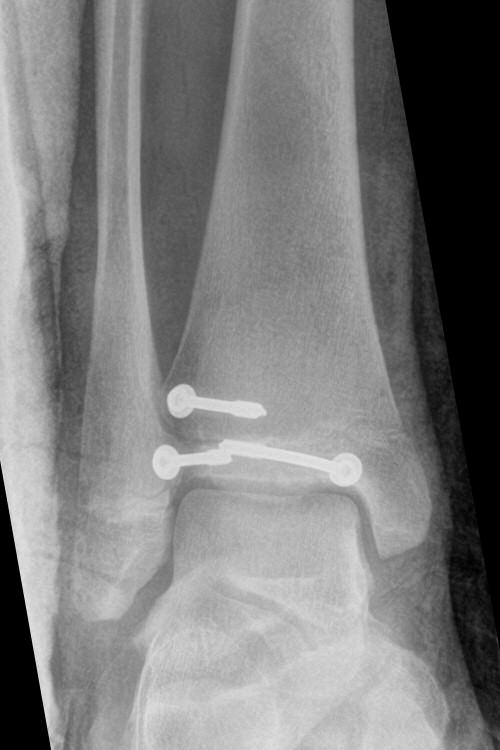

Exempel på triplansfraktur hos nästan färdigvuxet barn

Efter operation med skruvfixation

Distal tibiafyseolys SH 4 triplansfraktur (barn)

Triplanfraktur = triplansfraktur = treplansfraktur: fraktur i distala tibia som engagerar både metafys, fys och epifys. Kan vara 2, 3 eller 4 fragment. I 50 % av fallen är även fibula frakturerad [3].